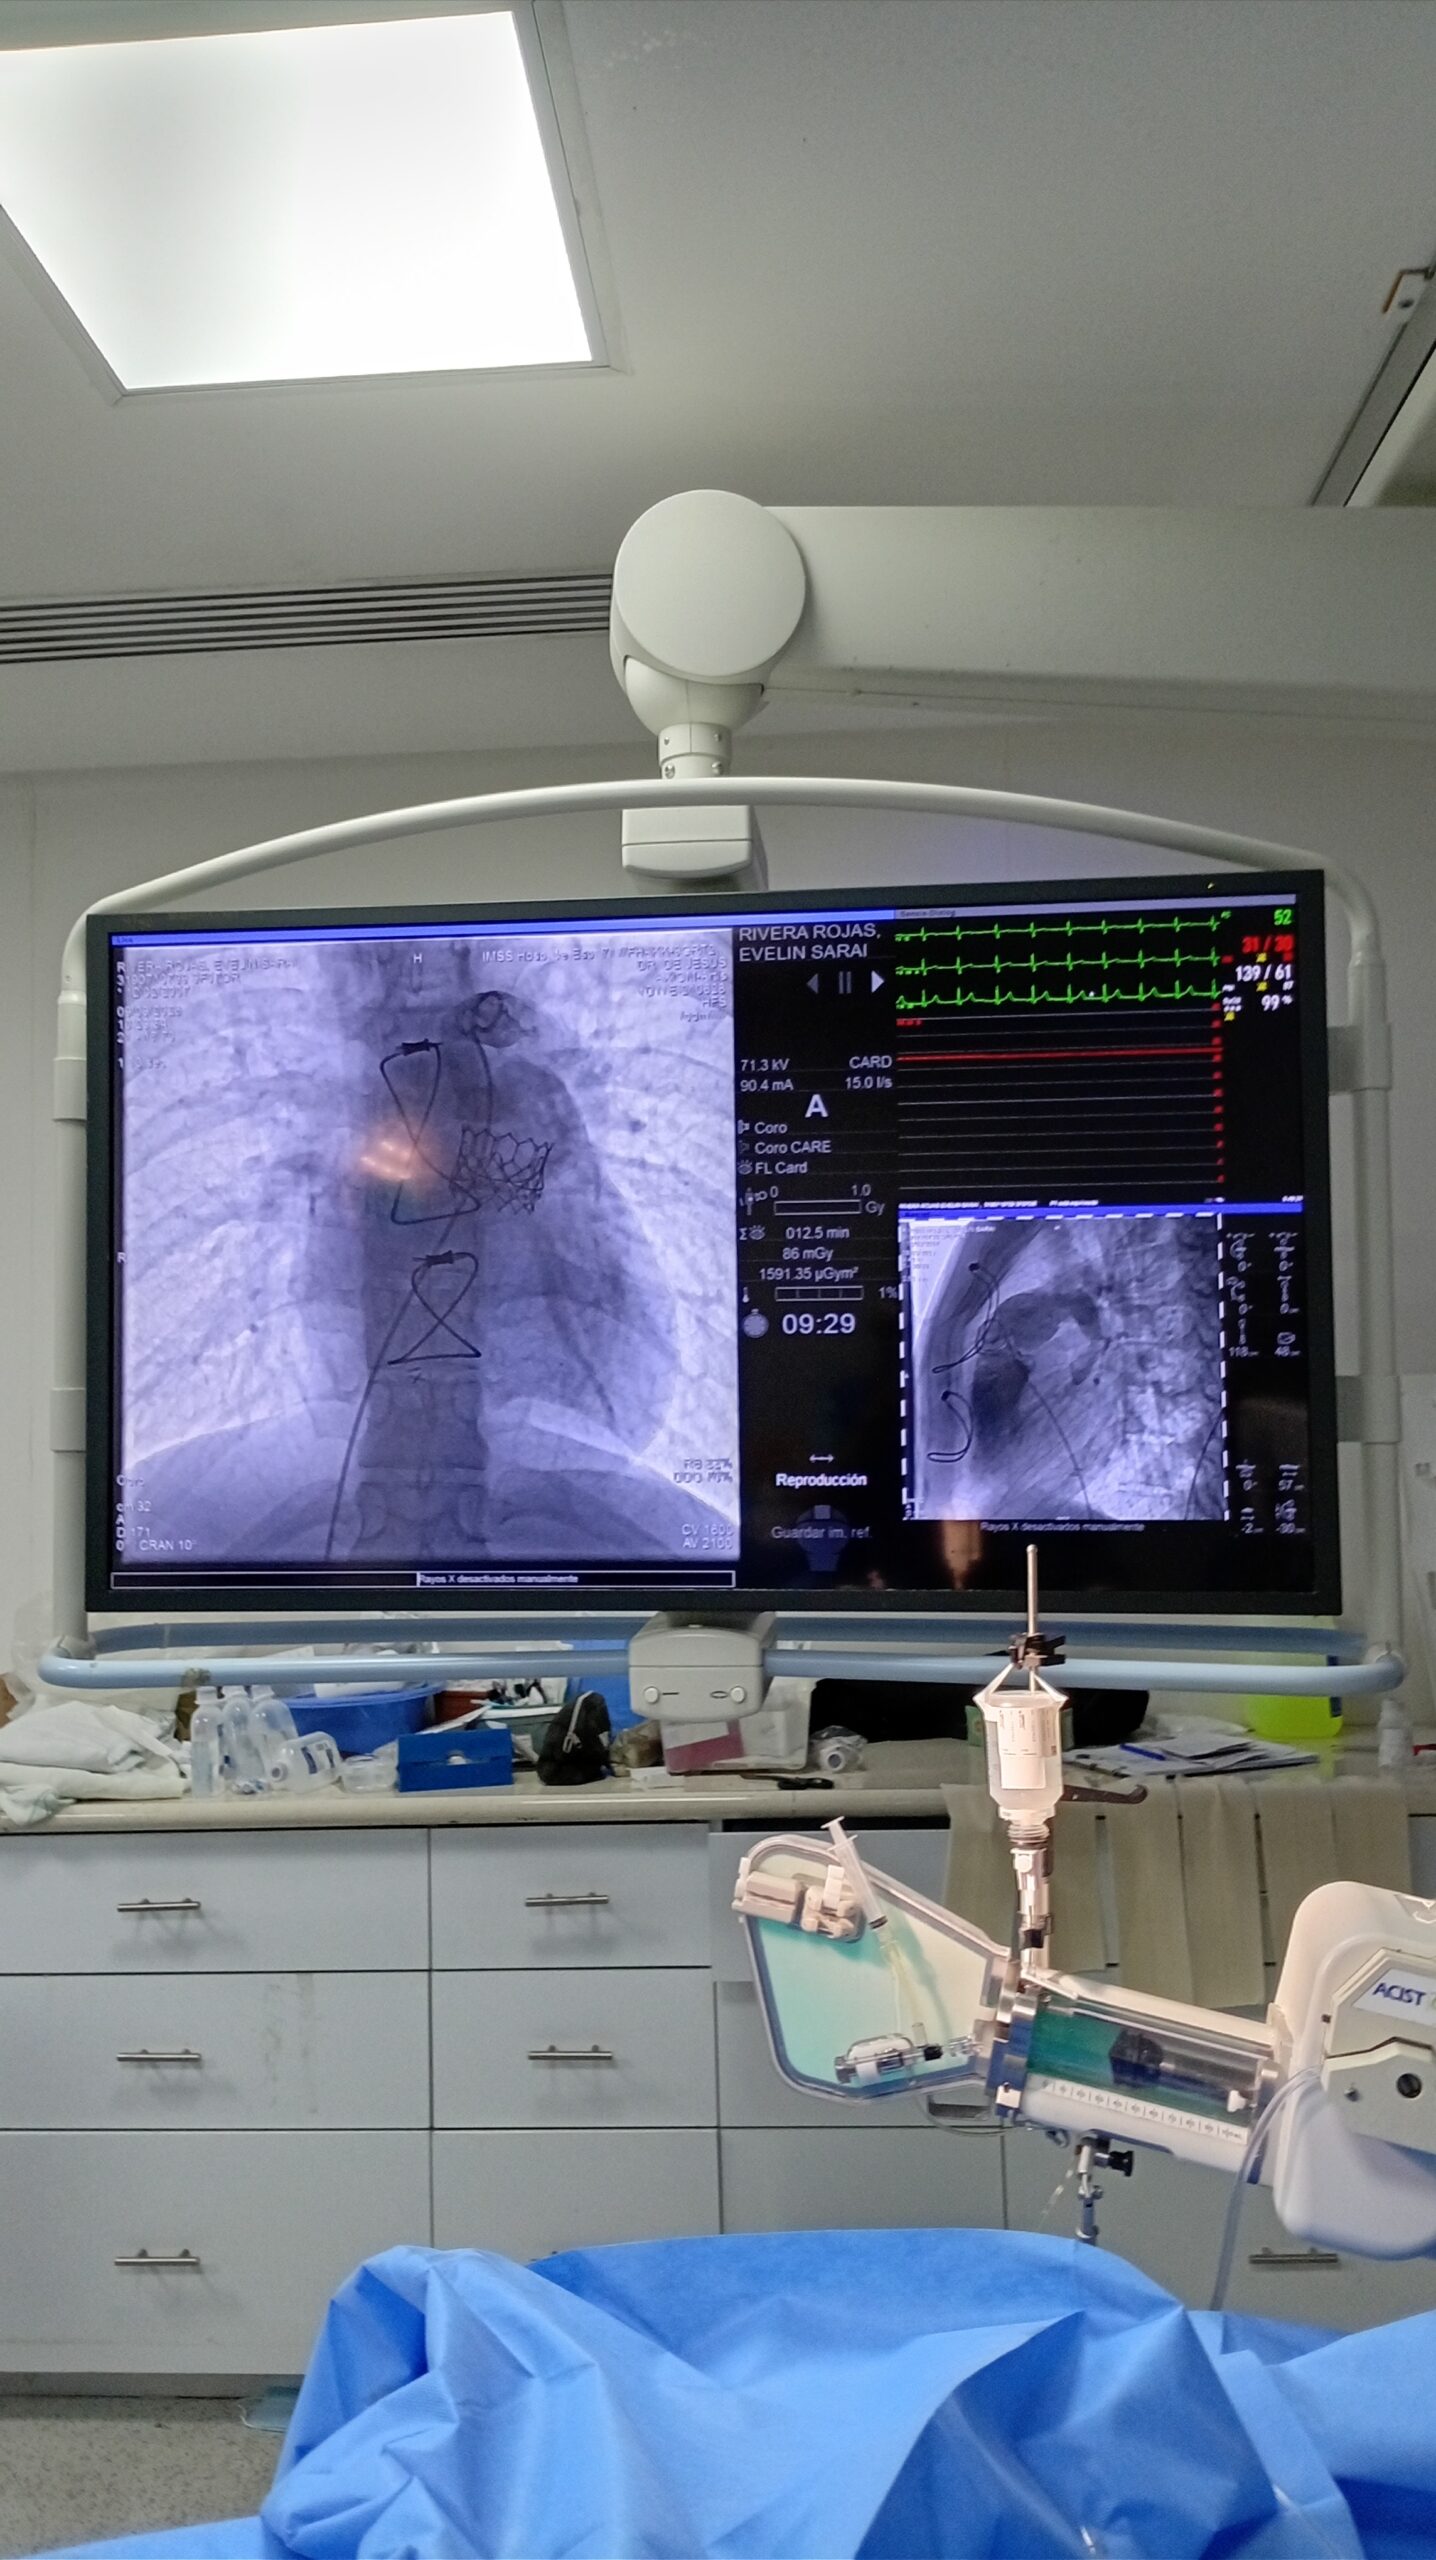

El jefe del Servicio de Hemodinamia de esta Unidad Médica, doctor Alberto Bazzoni Ruiz, explicó que el pasado 6 de marzo, Evelin N de 18 y Luis N de 19 años, ambos de Durango, fueron los primeros pacientes en ser intervenidos con este procedimiento que se realiza mediante una punción en la vena femoral (ingle) y por ahí se accede hasta el corazón para implantar la prótesis de la válvula que se va a reemplazar o reparar sin necesidad de abrir el tórax y exponer el corazón como se hacía en el pasado.

En marzo de este año, el doctor Teodoro de Jesús Alvarenga, cardiólogo intervencionista con alta especialidad en cardiopatía congénita y un equipo multidisciplinario encabezado por el doctor Bazzoni Ruiz realizaron la colocación de válvula pulmonar transcatéter a Evelin N y a Luis N; procedimientos que se efectuaron en menos de una hora en cada caso.